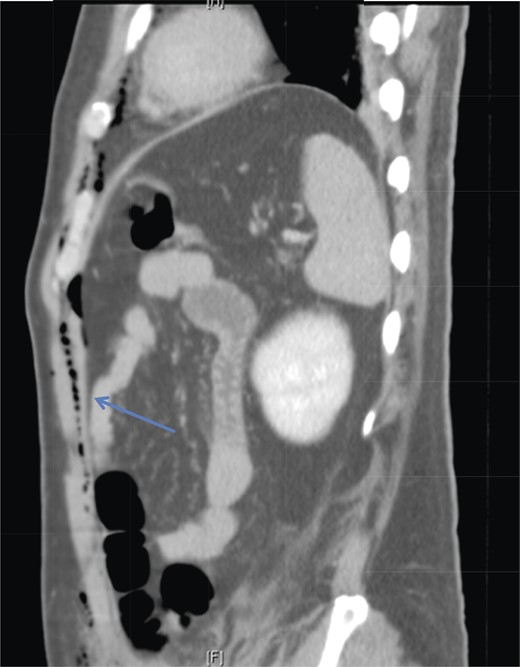

A 42-year-old male with a past medical history of hypertension was admitted for an elective TEP repair of his left inguinal hernia. Endotracheal intubation and general anesthesia were given uneventfully. The extraperitoneal space was developed with a balloon space maker, and insufflation of carbon dioxide at a maximum pressure of 12 mmHg was performed. Intraoperatively, a large incarcerated indirect left inguinal hernia containing omentum was reduced. A Optilene mesh (10 × 12 cm) was placed and tacked appropriately after hernia reduction. There were no obvious tears in the peritoneum and the total operative time was ∼90 min. No elevation of end-tidal CO2 was noted during the surgery and the patient was extubated successfully. The patient subsequently complained of left-sided chest pain on the same night of the surgery. He did not have abdominal pain. He had subcutaneous crepitus extending from the left groin to the left chest. His cardiac enzymes were negative and his electrocardiography revealed a sinus rhythm with no acute ischemic changes. A plain radiograph of the chest showed a sliver of lucency in the mediastinum suspicious for pneumomediastinum, with no obvious pneumoperitoneum or pneumothorax seen (Fig. 1). Computed tomographic (CT) imaging of the thorax and abdomen confirmed the radiograph finding of pneumomediastinum and diffuse subcutaneous emphysema tracking along the abdominal muscles bilaterally, as well as a small amount of free air and stranding in the left posterior pararenal space (Figs 2–4). The patient was treated conservatively with oral analgesia and supplemental oxygen. His chest pain resolved by the third postoperative day and he was discharged well. He was advised to avoid air travel for 1 month. He was reviewed in clinic at the 1-week and 1-month intervals and did not report any further chest pain or respiratory symptoms. His operation site healed well and he remained recurrence free.

Sagittal section of CT abdomen demonstrates air tracking along the anterior extraperitoneal space (arrowhead) into the anterior mediastinum and preperitoneal fat.

Laparoscopic CO2 can enter the retroperitoneal space and track along tissue planes into the pleural space and mediastinum [4]. Chien and Soifer [7] reported a case of pharyngeal emphysema complicating a laparoscopic hernia repair, and postulated that myopectineal dissection may lead to CO2 tracking retroperitoneally into the thorax. This is a possible cause of pneumomediastinum in our patient, as his CT imaging showed the presence of left posterior pararenal stranding, supporting a possible retroperitoneal dissection of CO2 to the thoracic cavity. Another pathway for transdiaphragmatic extension of air into the mediastinal space was proposed by Meyers [8]. The endothoracic fascia is continuous with the extraperitoneal space of the fascia transversalis. Extraperitoneal gas can dissect through the anterior gaps of the diaphragm between the sternal, xiphoid and costal origins of the diaphragm. With the aid of anatomical studies in cadavers, Kleinman et al. confirmed these observations [6]. This potential pathway likely explains the entry of CO2 from our patient's abdominal wall (extraperitoneal space) into the mediastinum, without the presence of pneumoperitoneum.